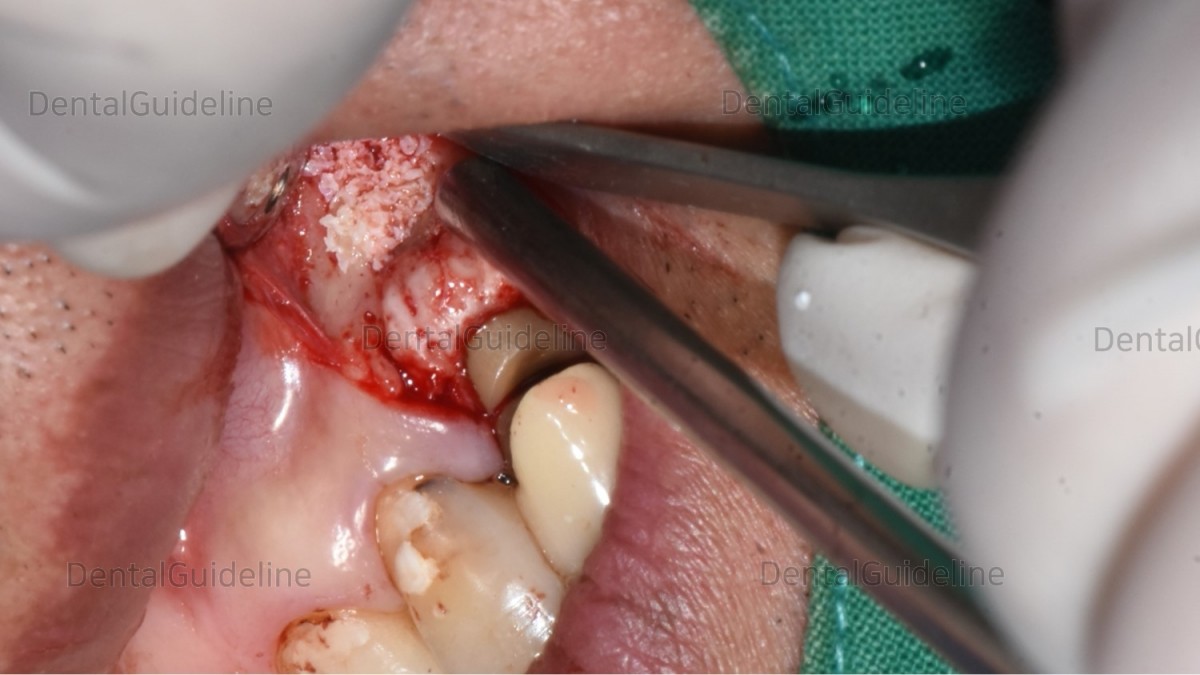

flap opening, lesion exposure.

The apical part was cut using a high-speed bur and the granulation tissue was curette out.